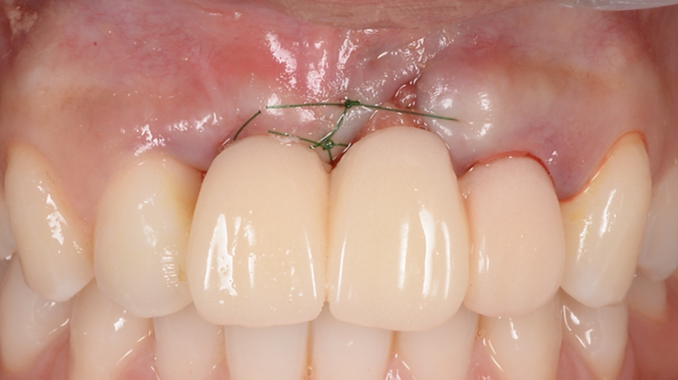

Clinical case: Patient-centered approach: treatment strategy for Root Membrane Technique & delayed implant placement

- Courtesy of Dr. Yoshiharu Hayashi, Japan -

Socket Shield Technique, anterior esthetics, maxillary anterior, esthetic, esthetics, delayed implant placement, socket preservation, AnyRidge, Root Membrane Kit, Root Membrane Technique, Partial Extraction Therapy, PET, esthetic zone, fuse abutment, Dr. Yoshiharu Hayashi,#11,#21,#22

Products:

AnyRidge implant system, fuse abutment Root membrane kit, PET Kit